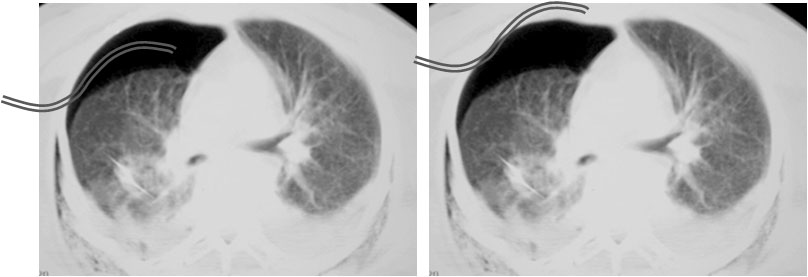

SIGNO DEL DIAFRAGMA AUSENTE

Signo de rotura diafragmática en TC, que consiste en la ausencia de un segmento del diafragma en uno o más cortes. La imágenes corresponden a un paciente con rotura traumática del hemidiafragma izquierdo. En la secuencia de cortes en la zona de transición toraco-abdominal no se ve el hemidiafragma izquierdo en ningún momento. Flecha roja: ángulo esplénico del colon herniado. Flecha blanca: estómago herniado con nivel hidroaéreo. Flecha verdenegra: bazo.